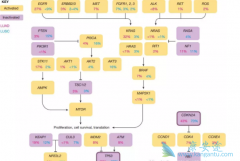

肺癌治疗可以通过生物标志物的检测来达到确定患者的具体类型,跟通用型肺癌治疗方案相比,生物标志物的治疗方法总的来说还是有许多优势的,因此,目前已成为 肺癌药物 开发过程中必不可少的一部分。通过检测生物标志物相关的指标,可以改善受试患者的定 ...

肺癌是全球致死率最高的恶性肿瘤,每年有众多患者死于肺癌。非小细胞肺癌(NSCLC),主要包括肺癌腺癌(LUAD)和 肺癌鳞癌 (LUSC)。吸烟是肺癌的高危因素,大多数肺癌与吸烟有关,其中LUSC与吸烟关系更为密切;不吸烟的肺癌患者以LUAD、女性和东亚人群 ...

肺癌分为小细胞肺癌和非小细胞肺癌,其中非小细胞肺癌又可以划分为 肺癌腺癌 、肺癌鳞癌和肺大细胞癌。其中每一种肺癌亚型的治疗措施都是不同一样的,但是目前而言,肺癌腺癌的靶向治疗最为成熟。肺癌亚型有较多的EGFR基因突变概率,可以使用吉非替尼、厄 ...